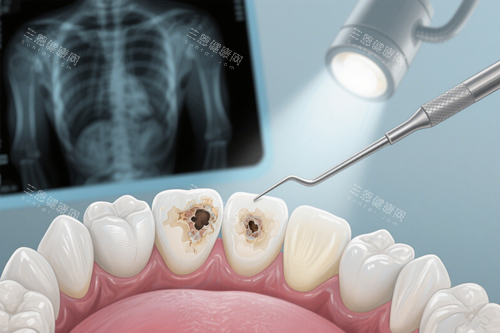

没等五分钟,张医生就过来接我了。他看着三十多岁,穿着白大褂特别精神,说话带着点青岛本地口音,一下子就拉近了距离。进治疗室前,护士小姐姐给我递了一次性鞋套和消毒后的围巾,还让我用漱口水漱口。治疗室里特别干净,仪器都摆得整整齐齐,墙面是淡蓝色的,让人感觉很放松。张医生先让我躺在治疗椅上,用一个小镜子仔细检查我的牙齿,还问我“平时是不是爱喝碳酸饮料?疼的时候是刺痛还是胀痛?”我一一回答后,他用可靠的仪器拍了个牙片,指着片子上的黑影说:“你这颗牙蛀得挺深的,已经快到牙神经了,幸好来得及时,还不用做根管治疗,补一下就能好。”

我一听不用做根管治疗,心里松了口气,之前听朋友说根管治疗又疼又费钱。张医生看出了我的紧张,笑着说:“别担心,咱们用的是不痛补牙技术,打麻药的时候就像被蚊子叮一下,一点都不疼。”他还详细跟我介绍了补牙的材料,有玻璃材料、树脂材料,还有进口的纳米树脂。“玻璃材料价格便宜,适合小孩或者临时补牙;普通树脂性价比高,耐磨度也够用;进口纳米树脂颜色和真牙几乎一样,硬度也更好,能用五到八年。”他没有推荐贵的,而是根据我的情况建议:“你这颗是后槽牙,平时咀嚼用力大,选普通树脂就够用了,经济又实用。”

确定好材料后,护士小姐姐给我涂上了医用凡士林保护嘴唇,张医生就开始准备补牙了。打麻药的时候真的像他说的那样,就轻微疼了一下,很快就没感觉了。他用可靠的工具一点点清理牙洞里的腐坏组织,动作特别轻柔,还时不时问我“有没有不舒服?要是疼就举手告诉我。”清理完后,他用生理盐水把牙洞冲洗干净,又用紫外线消毒,说这样能防止细菌残留。然后他调了树脂材料,一点点填进牙洞里,还用特殊的灯光照射固化,每固化一次就用工具修整一下形状,确保和其他牙齿贴合。